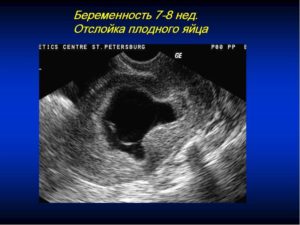

Отслойка визуализируется в виде анэхогенной структуры (не отражающей ультразвук) вокруг плодного яйца. Изменение его формы с круглой на овальную при обнаружении гематомы свидетельствует об угрозе выкидыша.

Патологическое состояние хорошо просматривается при помощи ультразвукового исследования. На экране монитора визуализируется гематома. Кровоподтек возникает по причине постепенного отслаивания и разрыва сосудов хориона от стенки матки. Очень часто женщина самостоятельно может заподозрить у себя симптомы отслоения.

Диагностировать данную патологию можно только при помощи УЗИ, на котором будет видно повреждение. По размерам гематомы можно определить степень риска для женщины и ребёнка и назначить соответствующее лечение в стационаре.